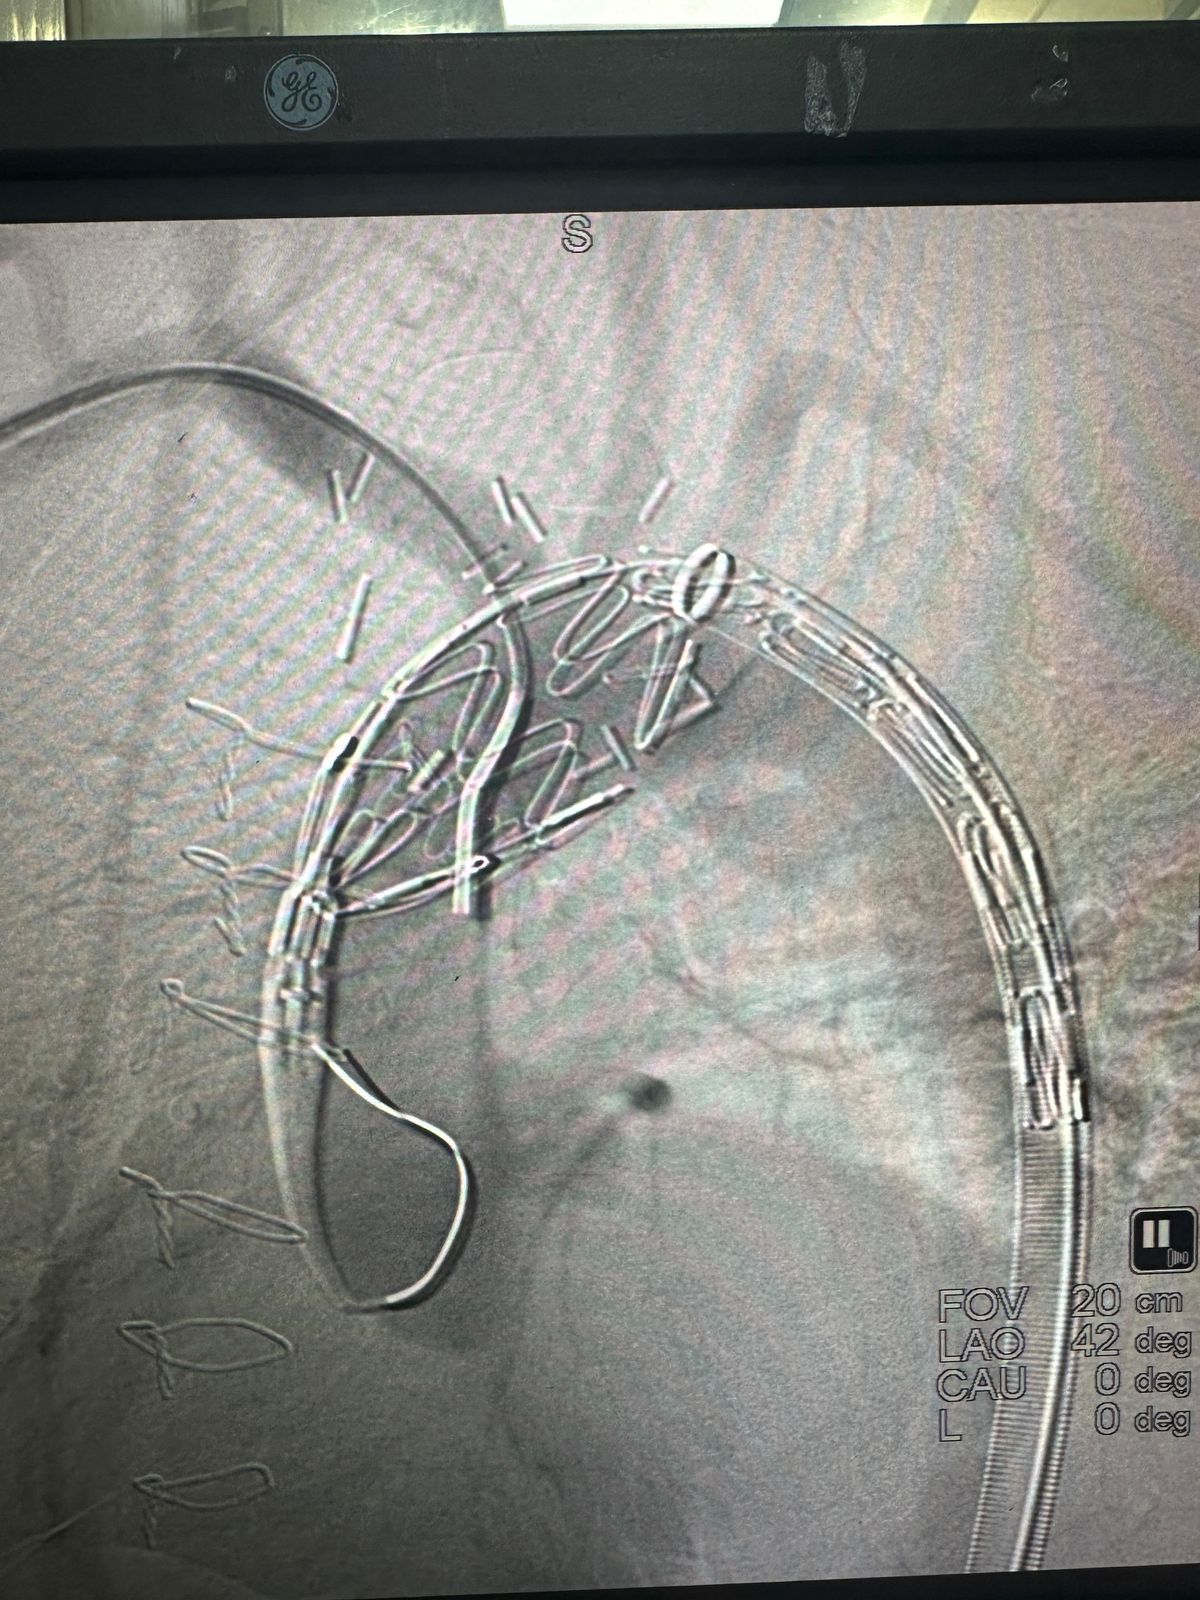

وتمثلت الحالة، بأول إصلاح داخل وعائي معدّل للقوس الأبهري والشريان الأبهري الصاعد في الأردن والمنطقة في إنجاز طبي نوعي يُعد الأول من نوعه في المملكة الأردنية الهاشمية والمنطقة.

وتمت إجراء الحالة بنجاح بتاريخ 16 فبراير 2026 من خلال إجراء تدخل وعائي معقد لعلاج أمّ دم كاذبة (Pseudoaneurysm) في القوس الأبهري ممتدة من الشريان الأبهري الصاعد لدى مريض يبلغ من العمر 35 عاماً يعاني من متلازمة بهجت ذات الاختلاطات الوعائية.

وكان المريض كان قد خضع سابقاً لجراحة مفتوحة لترميم الشريان الأبهري، وعانى لاحقاً من نوبات نزيف متكررة انتهت بنزيف حاد استدعى تدخلاً عاجلاً

وشارك في الإنجاز الطبي كل د. مأمون القريوتي – استشاري جراحة الأوعية الدموية ود. عدي الجعبري – اختصاصي الأشعة التداخلية